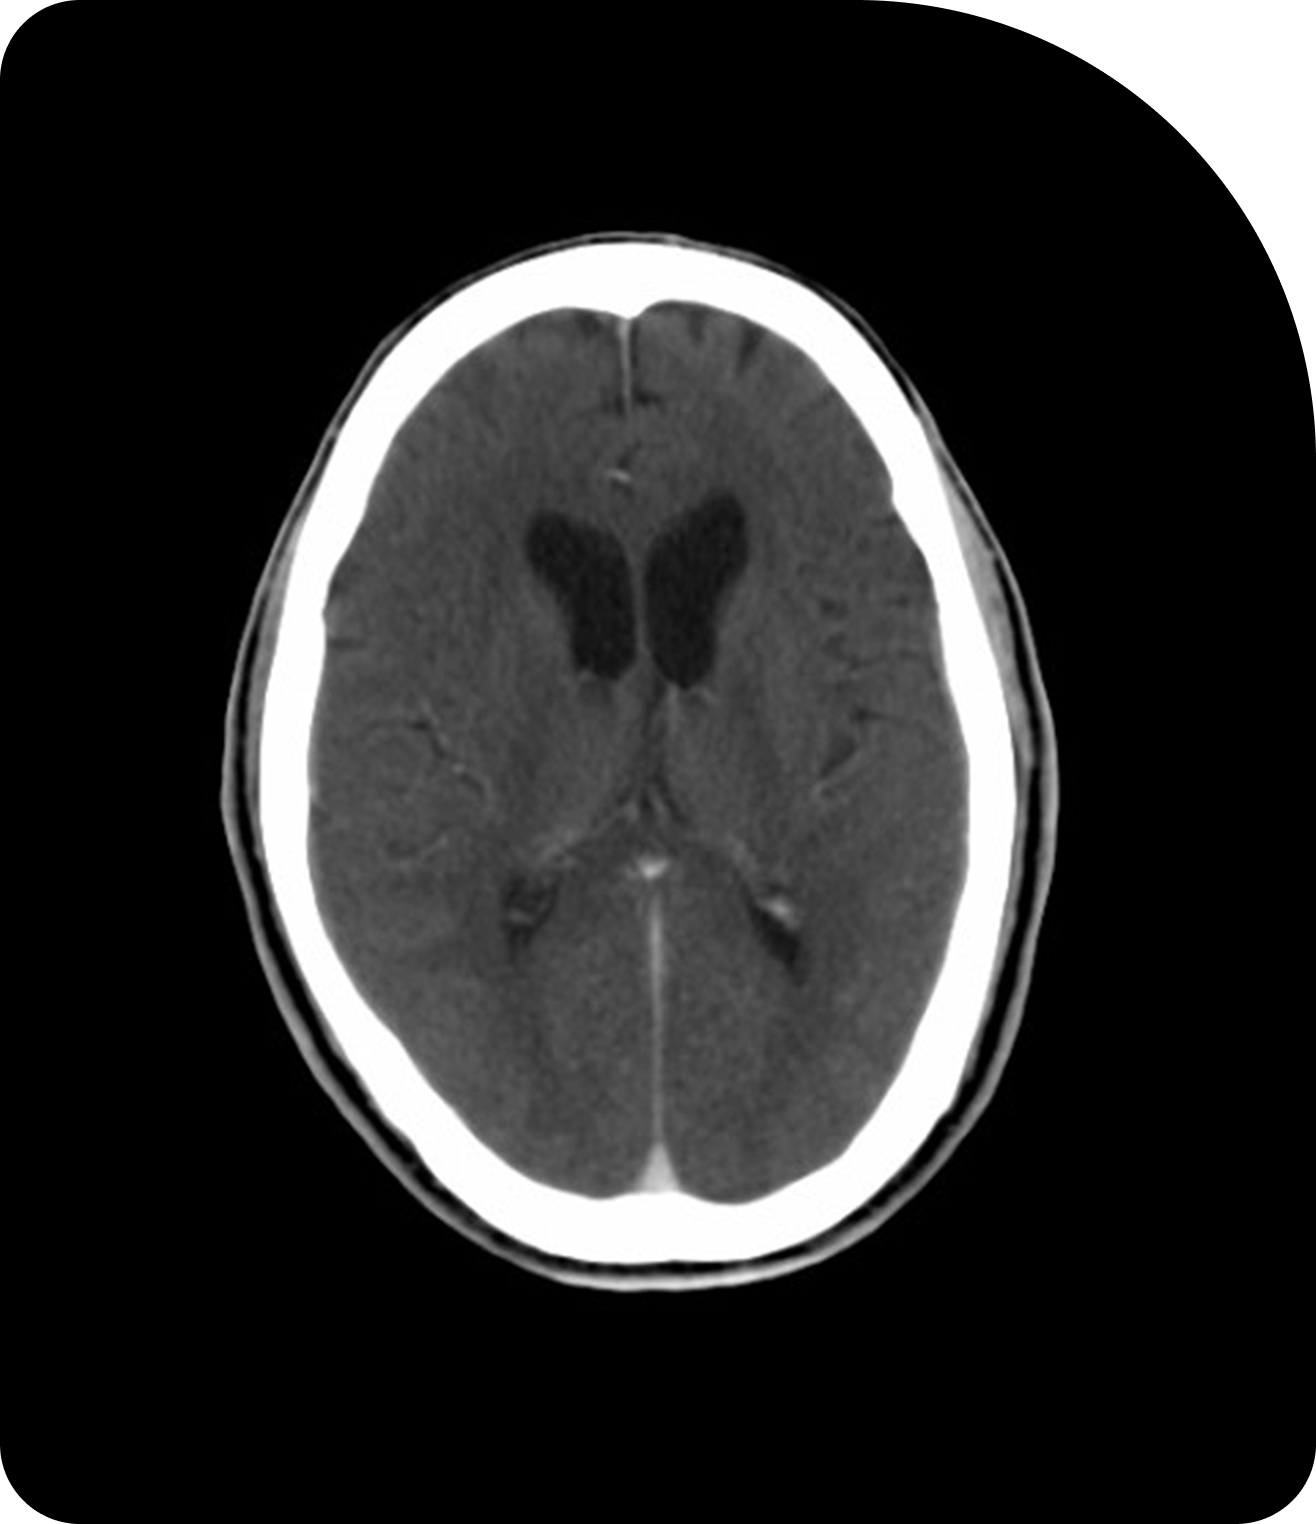

Des images plus claires signifient un ciblage plus précis. Comparez la tomodensitométrie (TDM), la tomodensitométrie volumique à faisceau conique (CBCT) et l’imagerie par résonance magnétique (IRM) pour constater la différence.

CBCT

La TDM à faisceau conique ajoute l’imagerie en salle pour soutenir la préparation quotidienne des patients.